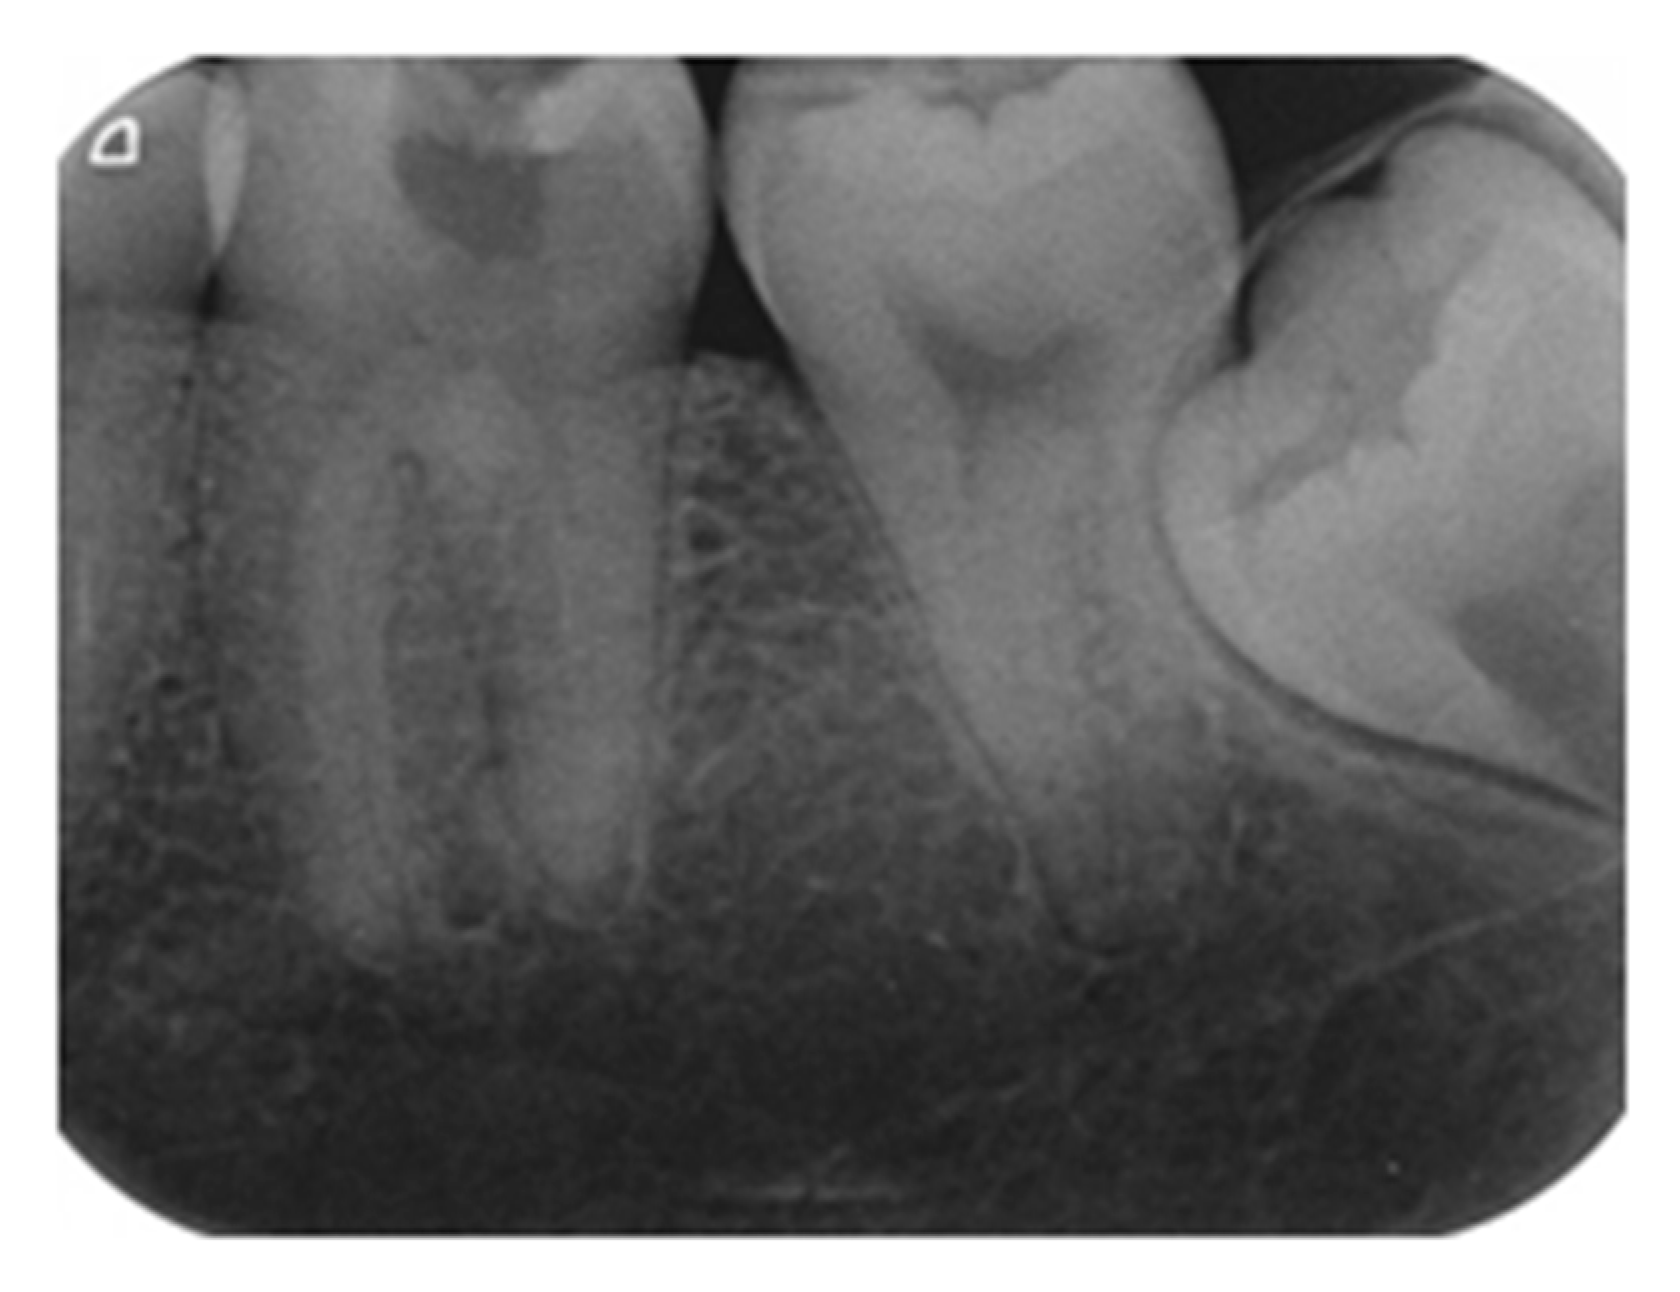

4.3. Endpoint of Carious Dentine Excavation

4.4. Indirect Pulp Capping

- Demant, S.; Dabelsteen, S.; Bjørndal, L. A macroscopic and histological analysis of radiographically well-defined deep and extremely deep carious lesions: Carious lesion characteristics as indicators of the level of bacterial penetration and pulp response. Int. Endod. J. 2021, 54, 319–330. [Google Scholar] [CrossRef]